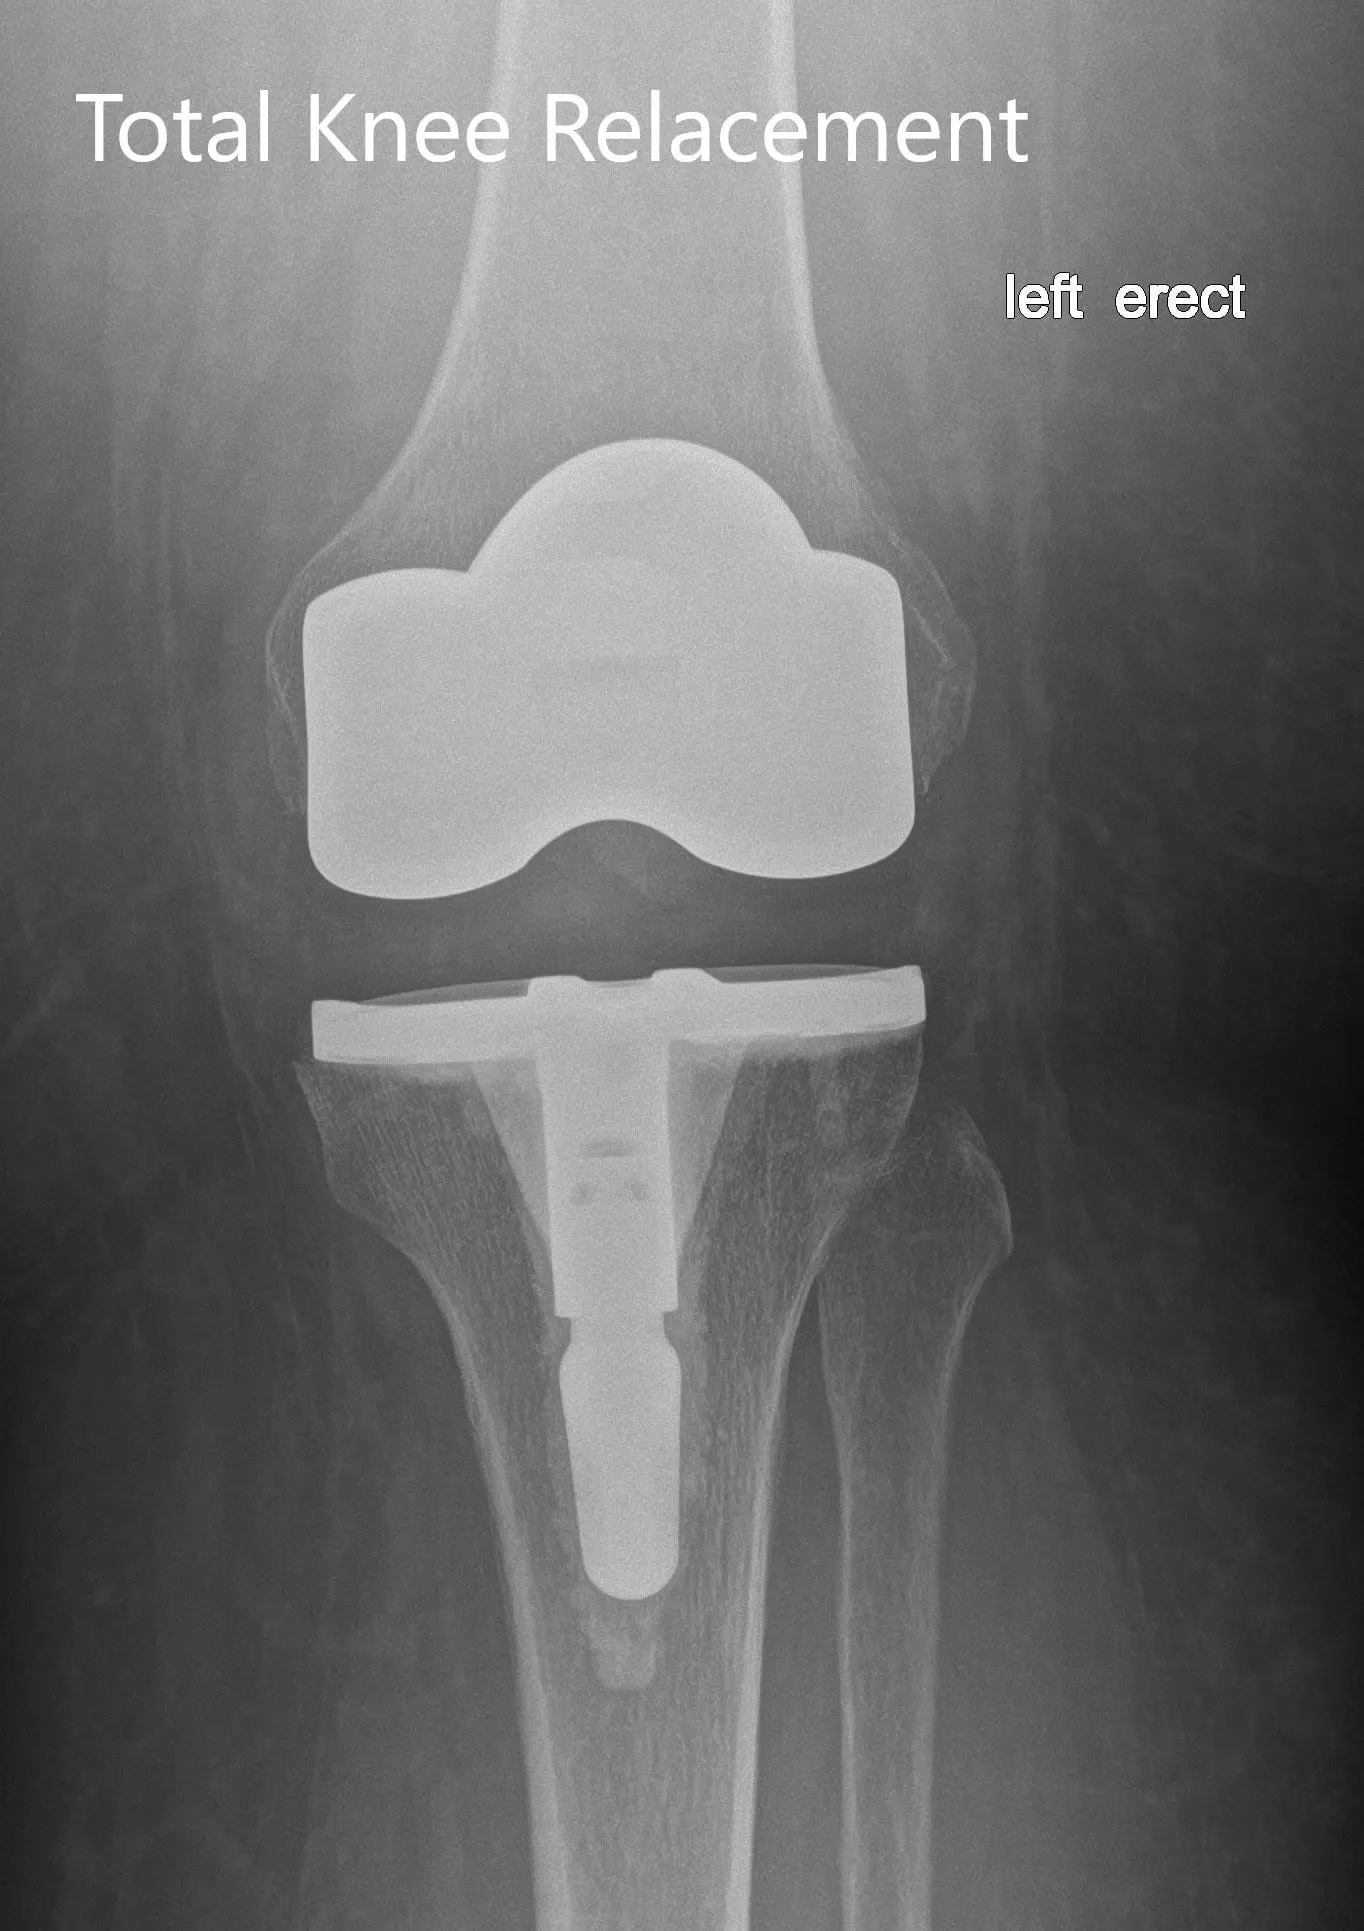

Postoperative X-ray of the left showing the anteroposterior and lateral view with total knee prosthesis in position

IMPLANTS USED: Posterior stabilized 8 left standard femoral component left-sided with tibia E left cemented with 14 x 30 stem with poly 16 mm with a 29-mm diameter poly patella.